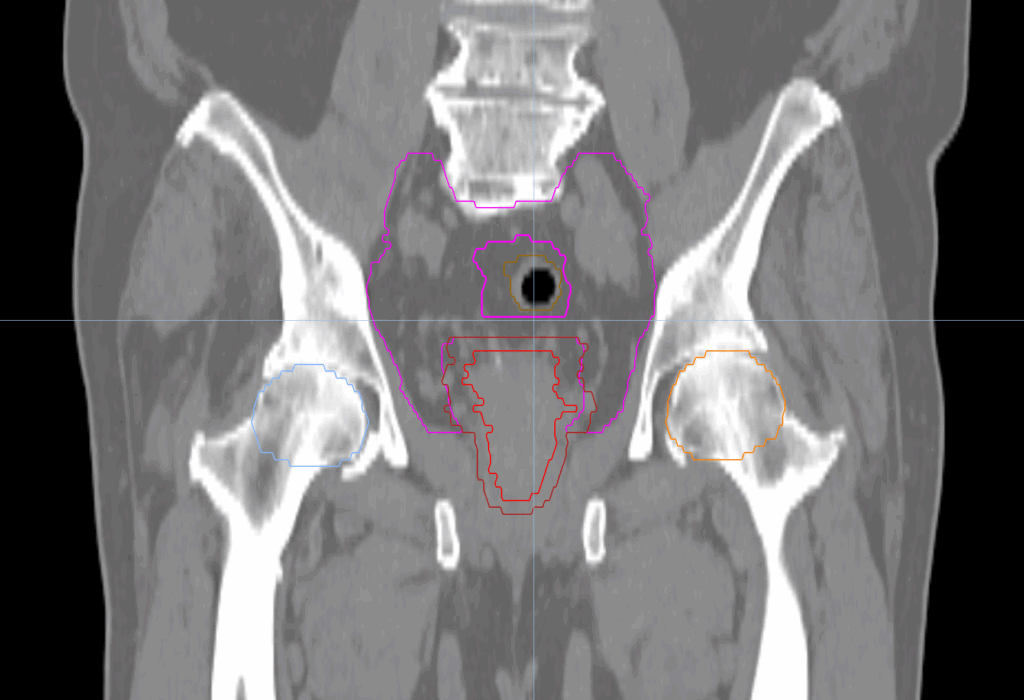

Planning CT Images